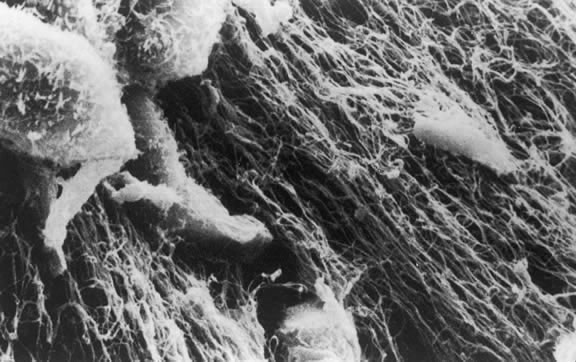

The anterior vitreous cortex or anterior hyaloid is the anterior surface layer or condensation of the vitreous body. There is no specialized membrane that constitutes the anterior vitreous cortex, but instead there is a greater density of collagen fibrils. Microscopically, the framework of collagen fibrils that run throughout the vitreous body ends in an interwoven network to form the anterior vitreous cortex. The superficial fibrils tend to run parallel to the surface in this region. The smooth surface and membrane-like appearance are due to the lamellar distribution of the cortical fibers and the associated highly polymerized mucoproteins.4,5 Anatomically, the anterior hyaloid forms the posterior limits of the posterior chamber. This portion of the vitreous cortex functions in the physiologic communication between the vitreous cavity and the aqueous humor. The anterior surface of the vitreous body separates from the pars plana approximately 1.5 mm anterior to the ora serrata. It extends medially to contact the lens posterior to the lens equator. Thus, the anterior hyaloid is in contact with the ciliary processes and the lens zonules, as well as the posterior lens capsule. The vitreous attaches to the lens capsule in a ring-like manner, forming the hyaloideocapsular ligament of Wieger. This ligament is believed by some to be synonymous with the attachment ring of the posterior zonular fibers.4 The circular area of attachment measures approximately 9 mm in diameter and is especially firm in younger persons or after intraocular inflammation.5 In this circular area the anterior hyaloid is thickened. Central to the attachment of Wieger's ligament (also known as Egger's line), the vitreous lens attachment is less pronounced and appears to be due to surface tension. This central area contains a potential space within the 9-mm ring known as Berger's space, or the patellar fossa. The anterior hyaloid then turns posteriorly to form the anterior portion of Cloquet's canal in the midportion of Berger's space. Cloquet's canal represents the remnants of the primary vitreous and can sometimes be seen with the slit lamp. It arises from the optic disc in a funnel-shaped manner, in the area of Martegiani, and extends forward to the posterior lens surface. The canal is 1 to 2 mm in width and has a down turn in the central vitreous cavity. The area of contact with the posterior lens capsule can at times be identified by a tag of embryonic tissue, known as a Mittendorf dot, located slightly nasal to the posterior pole of the lens. Similarly, a remnant of the posterior primary vitreous can occasionally be identified on the optic disc. This remnant, representing the embryonic point of exit of the hyaloid vascular system from the optic nerve head, is known as Bergmeister's papilla. The walls of Cloquet's canal are formed by a vitreous condensation rather than a true membrane (see Fig. 1).

In the vitreous base, collagen fibers are relatively coarse, are numerous, and insert perpendicularly to the retina and pars plana. These fibers consist of collagen fibrils with diameters of 10.8 to 12.4 nm.16 The microscopic detail of the vitreous fibers attachment to the vitreous base varies from anterior to posterior. Anterior to the ora the fibers are less dense than posterior to the ora. Electron microscopic studies by Gartner17 demonstrate that the vitreous fibers have complex interdigitations with the reticular fibrillar materials of the basement membrane of the nonpigmented ciliary epithelium but do not pass between the cells. The anteriormost fibers splay out anteriorly to form the anterior loop of the vitreous base, which is important in the pathogenesis of anterior PVR.18 Posterior to the ora, bundles of vitreous fibrils attach to the ILM. Cords of vitreous collagen insert into gaps between the neuroglia. Gloor and Daicker19 likened this arrangement to Velcro and suggested that this may explain the strong vitreoretinal adhesion of the vitreous base. Cellular elements are also present in the vitreous base. Fibroblast-like cells are present anterior to the ora, and macrophage-like cells are posterior to the ora.17 These cells may play a role in the hypocellular gel contraction that characterizes anterior PVR.